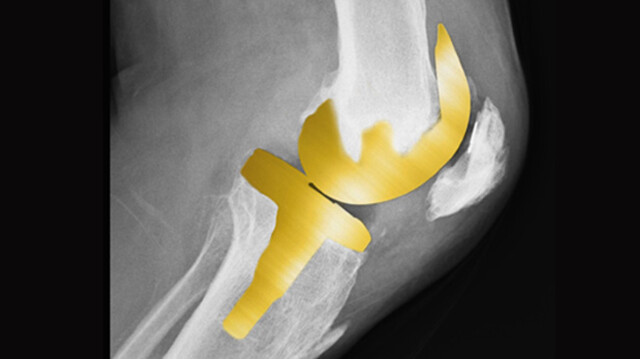

ही सर्जरी आता भारतात फार मोजक्याच रुग्णालयात उपलब्ध आहे. यामध्ये ‘गुडघे प्रत्यारोपण’च्या पार्टला टिटॅनिअल निओबियम नायट्रेट (पोरेक्स) हे कव्हर लावल्यावर त्याचा रंग गोल्ड प्लेटेडसारखा सोनेरी दिसतो. त्यामुळे याला ‘गोल्डन नी रिप्लेसमेंट’ असं नाव देण्यात आलं आहे. यामुळे रुग्णाला कोणत्याही अॅलर्जीचा त्रास होत नाही. नवी मुंबईत अशाप्रकारची गोल्डन नी रिप्लेसमेंट सर्जरी होण्याची ही पहिलीच वेळ असेल, असा दावा डॉ. शैलेंद्र पाटील यांनी केला आहे.